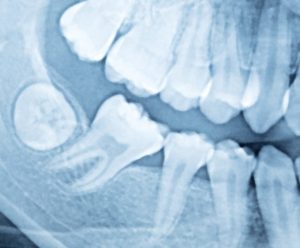

La retracción de la encía es una condición común en la que el tejido gingival se desplaza, dejando expuesta la raíz del diente. Esto no solo afecta la estética de la sonrisa, sino que también puede provocar sensibilidad dental, mayor riesgo de caries y pérdida ósea.

Las cirugías dentales estéticas son una de las soluciones más efectivas para tratar este problema. Si no se aborda a tiempo, la retracción puede empeorar, causando complicaciones bucodentales más graves.

Es importante saber que la encía no vuelve a crecer por sí sola. Para corregir el defecto estético y funcional, se suele recurrir a un injerto gingival, tras eliminar primero la causa subyacente (como la periodontitis o el cepillado agresivo).

La movilidad dental puede estar relacionada con la retracción de encías. Cuando el tejido que rodea la raíz del diente se deteriora, el diente pierde estabilidad y puede moverse durante la masticación. Esto no solo causa incomodidad, sino que también indica una posible enfermedad periodontal avanzada.

Uno de los efectos más visibles de la retracción gingival es la apariencia de “dientes largos”. Esto ocurre cuando la encía se retrae y deja expuesta una parte inusual de la raíz. Las causas pueden ser genéticas, enfermedades periodontales, cepillado agresivo o ortodoncia mal realizada.